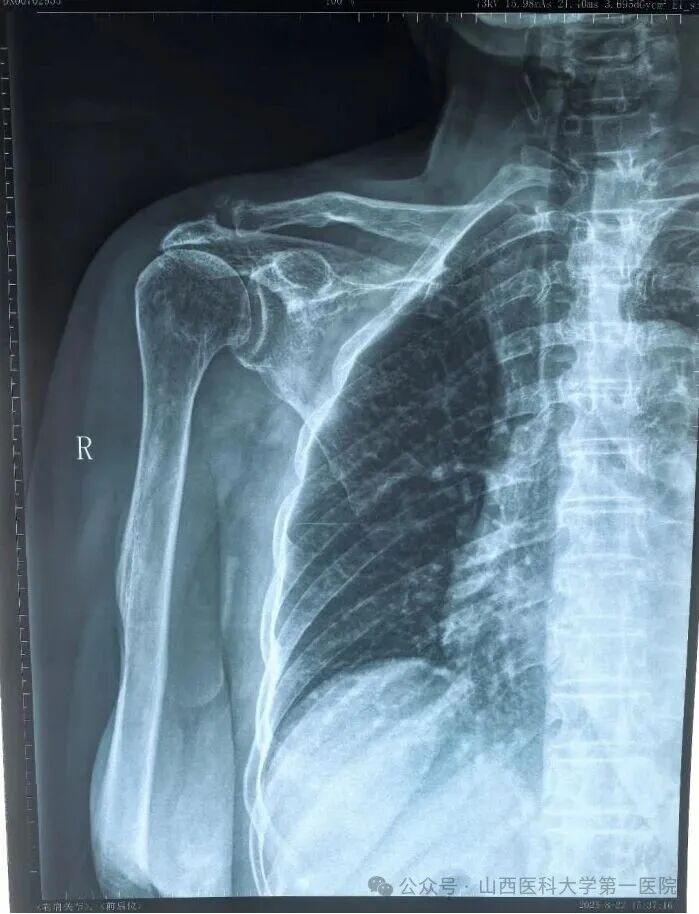

郭女士术前右肩关节正位片显示肱骨头上移明显